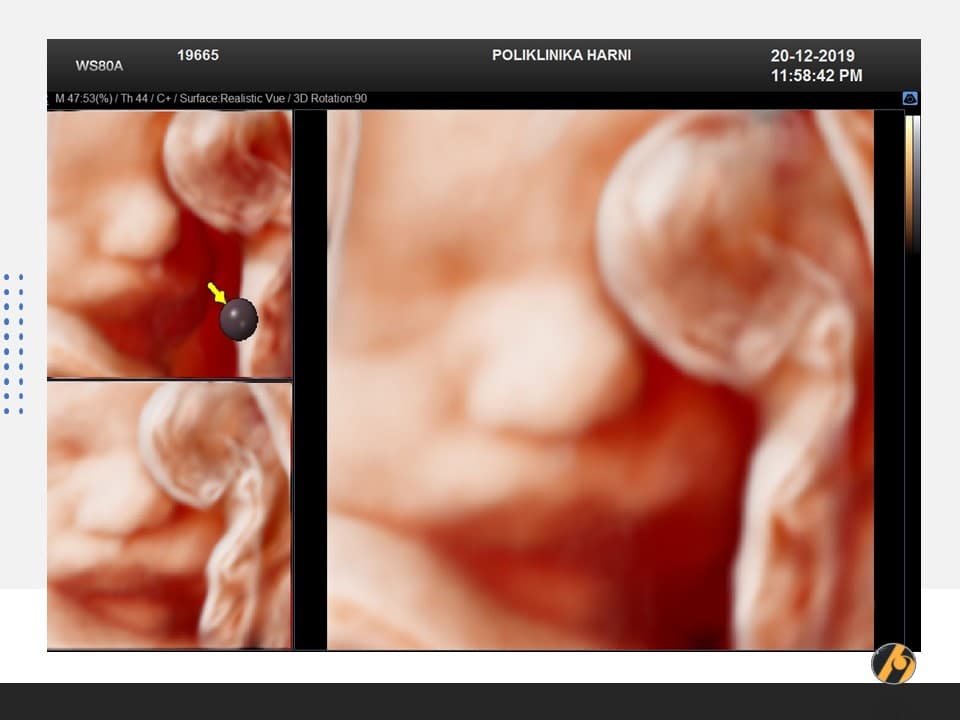

U 39. tjednu trudnoće beba je potpuno razvijena i spremna za život izvan maternice.

Prosječna duljina bebe iznosi oko 50 centimetara, a težina se obično kreće između 3200 i 3600 grama, iako su moguće individualne razlike. Potkožno masno tkivo sada je dobro razvijeno i pomaže bebi u održavanju tjelesne temperature nakon rođenja.

Pluća su u ovoj fazi funkcionalno zrela, dok mozak i živčani sustav nastavljaju sazrijevati i nakon rođenja. Beba ima razvijen refleks sisanja i hvatanja koji će joj omogućiti hranjenje majčinim mlijekom i prve interakcije s roditeljima.

Većina beba sada je u položaju glavom prema dolje, što je najpovoljniji položaj za vaginalni porod. Prostor u maternici postaje vrlo ograničen pa su pokreti drukčiji nego ranije u trudnoći. Oni su sporiji, ali često snažni i jasno osjetljivi.